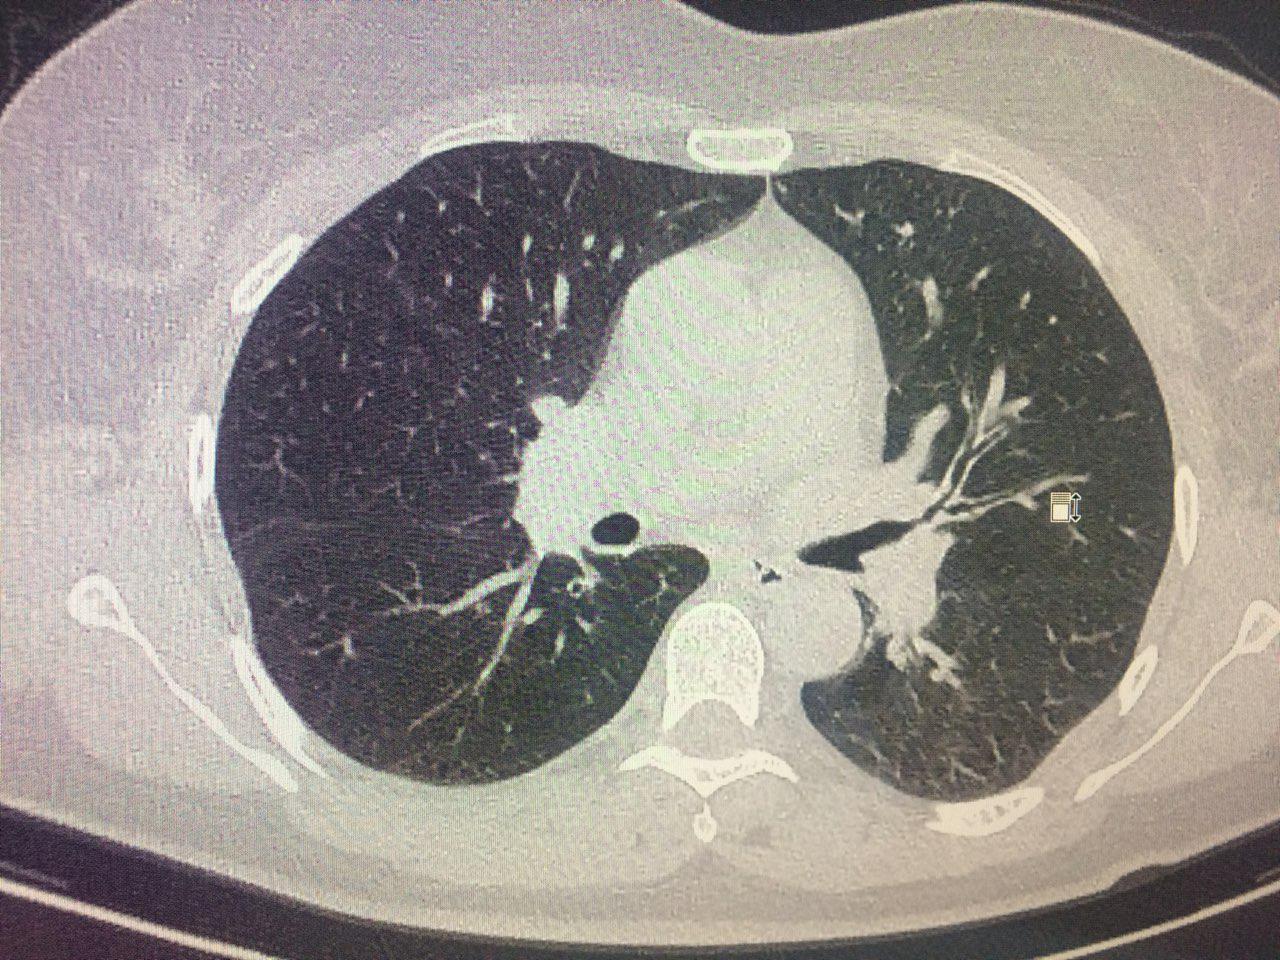

Фотографии и снимки КТ легких без контрастных веществ

Раздел: Визуальный дайджест